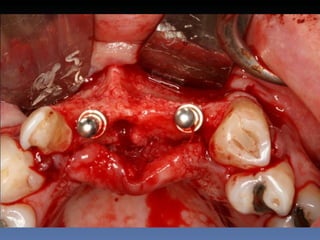

Diagnóstico: Desdentado parcial

pré-maxila.

Plano de tratamento: Reabilitação pré-maxila com

instalação de 2 implantes endo-ósseos (1.1,.2.2), para

reabilitação protética fixa.